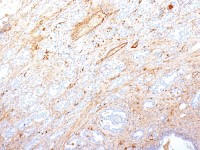

IHC-P analysis of mouse spleen tissue using GTX11944 TREM1 antibody.